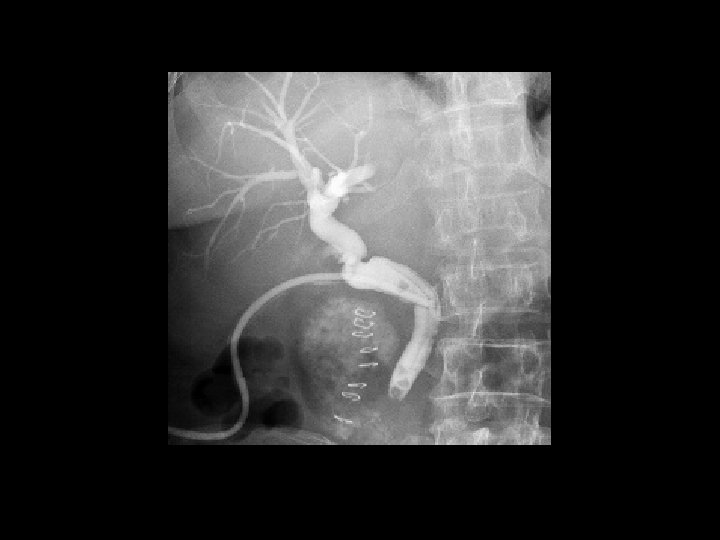

FLUOROSCOPY IMAGES IN MOTION